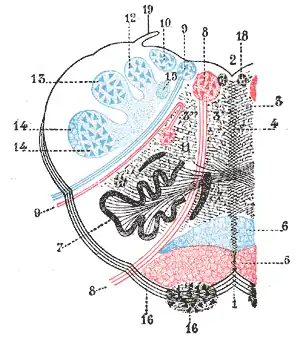

La portion dorsolatérale de la moelle allongée est vascularisée par l’artère cérébelleuse postérieure inférieure (PICA) et contient entre autres les noyaux vestibulaires, les fibres descendantes hypothalamiques (contrôle du système nerveux autonome sympathique), le noyau du nerf trijumeau spinal et son tractus, le noyau ambigu (noyau du moteur des nerfs IX, X et XI[1]), le pédoncule cérébelleux inférieur et les fibres du système antérolatéral (spinothalamique, spinoréticulaire et spinomésencéphalique).